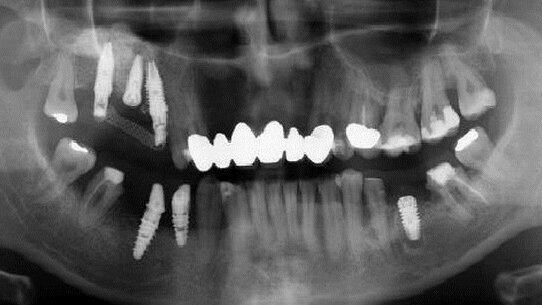

Si è presentato un paziente di sesso maschile chiedendo che venisse ricementata una vecchia corona in oro ceramica in corrispondenza del dente 2.5: in realtà si era decementato il relativo perno moncone e un’accurata ispezione della radice ha mostrato una rima di frattura della stessa. Su richiesta del paziente si è comunque proceduto alla ricementazione del manufatto rinviando ulteriori terapie. Dopo 2 mesi il paziente si è presentato di nuovo lamentando dolore e gonfiore in corrispondenza della gengiva del dente in questione, con fuoriuscita di materiale purulento dal tragitto fistoloso presente a livello vestibolare (Fig. 11).

Le valutazioni radiologiche mediante OPT ed endorale hanno evidenziato l’estensione della lesione periapicale e rafforzato il sospetto di una frattura radicolare (Fig. 12). Dopo aver ottenuto il consenso del paziente all’estrazione e al possibile inserimento di una fixture, si è proceduto alla avulsione della radice e del tessuto di granulazione a essa adeso (Fig. 13). Si è quindi proceduto alla scolpitura del lembo vestibolare che ha mostrato un importante deficit osseo (Fig. 14) che tuttavia non ha impedito l’inserimento di una fixture BTI universale esterna (lunghezza 15 mm, diametro 4 mm) stabilizzata solo a livello apicale (Fig. 15). Si è quindi proceduto a ricostruzione della parete vestibolare mediante innesto di osso eterologo (OsteoXenon®, Bioteck Italia) miscelato con PRGF.

A copertura dell’innesto sono state posizionate membrane autologhe di PRGF e di fibrina suturando il lembo vestibolare senza incisione di scarico del periostio (Figg. 16,17): infatti una volta posizionate le membrane gelificate il lembo vestibolare ha immediatamente riacquisito quella elasticità tissutale che ha permesso di evitare il rilascio periostale. Ne consegue in tal modo una minor morbidità post-operatoria (ricordiamo infatti che è proprio l’incisione del periostio una delle cause maggiori di edema e di ematomi cutanei), nonchè la preservazione di quella struttura fondamentale per la rigenerazione di nuovo osso: per questo motivo non è stato necessario inserire membrane sintetiche a protezione dell’innesto. A copertura della fixture è stato posizionato un abutment di guarigione transmucoso suturando il lembo attorno a essa. Il processo di guarigione non ha avuto problemi e l’uso di FANS è stato ridotto a una sola dose di ibuprofene nelle ore successive all’intervento. Dopo 2 mesi (Figg. 18,19) si è proceduto a rimuovere il tappo di guarigione e la fixture non ha mostrato alcun segno clinico (dolore, mobilità) di mancata osteointegrazione: ciò nonostante si è preferito protesizzare l’impianto solo dopo 5 mesi (Figg. 20, 21). Il follow-up a 18 mesi dall’inserimento della fixture (a causa degli gli impegni lavorativi del paziente) ha mostrato la stabilità del risultato sia da un punto di vista clinico che radiografico (Figg. 22, 23), potendo a quel punto proseguire con l’esecuzione del manufatto definitivo.